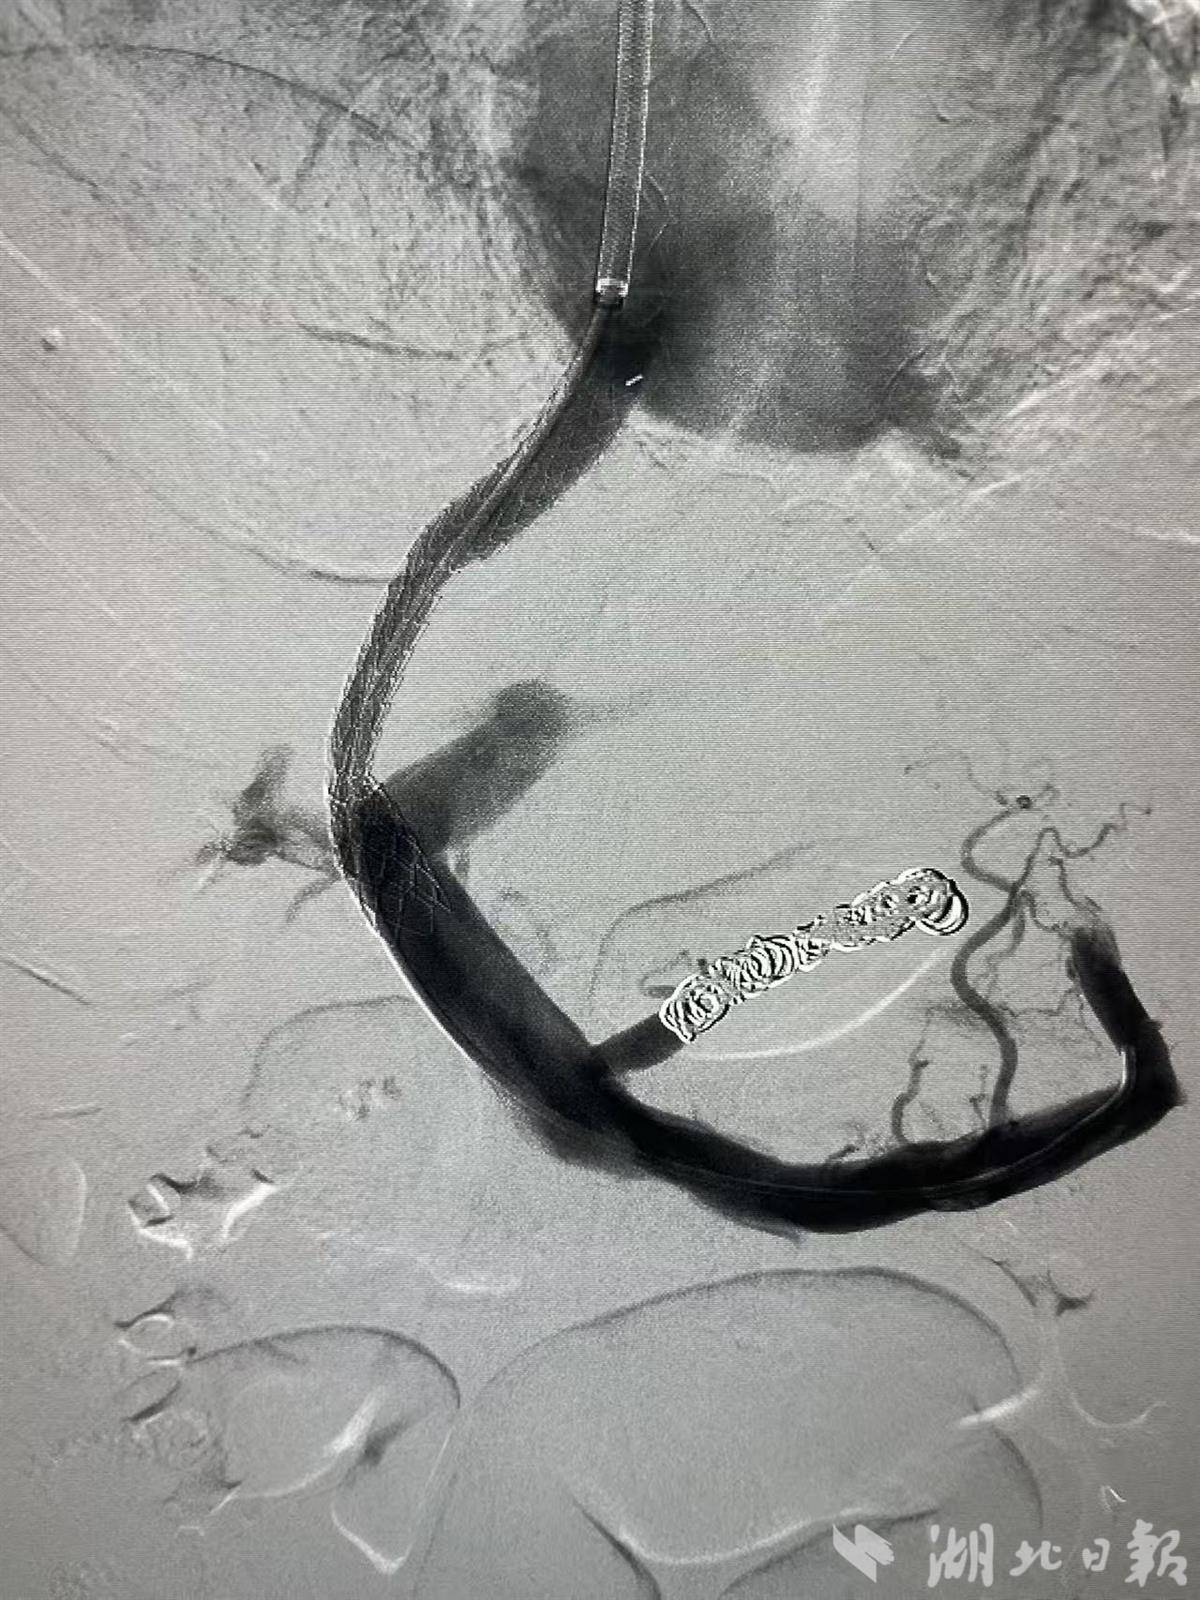

支架植入后,门脉压力下降明显

肝病科徐建良主任医师与放射科徐庆副主任医师团队迅速启动多学科会诊。专家们评估后认为,必须从源头上为门静脉这条“高压河流”进行“疏浚降压”。经与家属充分沟通,团队决定为其施行“经颈静脉肝内门体分流术”,即TIPS手术。手术中,在血管造影系统DSA设备引导下,专家们犹如在肝脏内部进行精密的“管道施工”,通过颈静脉这个微小入口,成功在患者的肝内建立了一条连接门静脉与肝静脉的“分流隧道”,并植入支架。术中造影清晰显示,术后门静脉压力显著下降,原来严重曲张的胃底静脉也随之萎缩。手术效果立竿见影,高先生术后大便颜色恢复正常,精神状态好转,顽固的腹水也得到了有效控制。